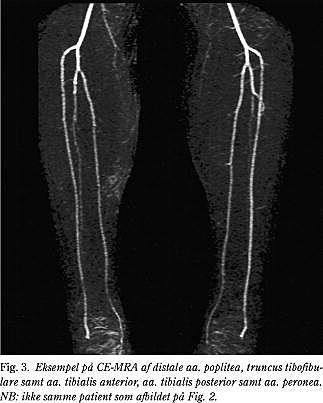

MRA med kontrast (CE-MRA)

Siden introduktionen af kontrastforstærket MRA (contrast enhanced MRA, CE-MRA) i midten af 1990'erne, er mængden af MRA-studier vokset støt (Fig. 3 og Tabel 1). Undersøgelsestiden er reduceret til 20-30 min for en komplet aorta til fod-undersøgelse. Da optagelsestiden for et enkelt karsegment, hvor informationerne til billeddannelsen opsamles, tager ca. 20 s kan undersøgelsen gennemføres under inspirationspause. Derved minimeres risikoen for bevægelsesartefakter. Pulsationsartefakter og artefakter pga. slyngede arterier ses ikke .